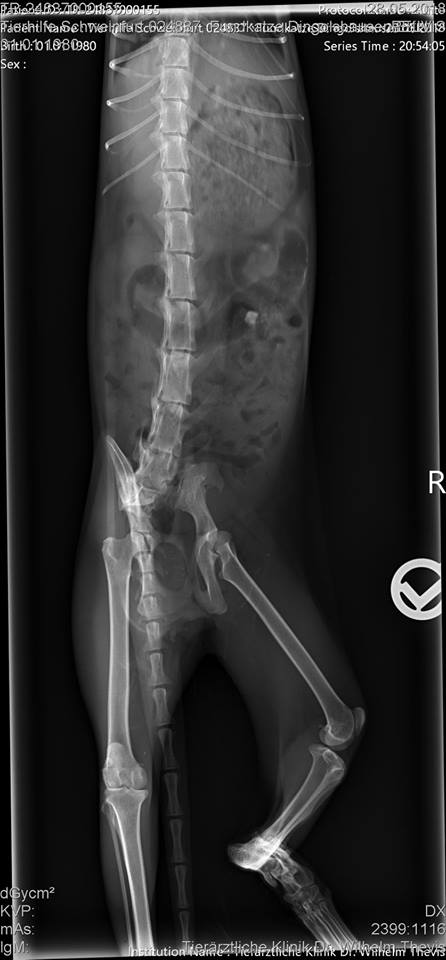

Dort stellte sich heraus, dass die Mieze tatsächlich einen Unfall hatte, jedoch schon vor einer Weile. Die Knochen sind jedoch leider alle krumm zusammen gewachsen, da sie wohl nie behandelt wurde :(. Nicht auszumalen, was die Süße an Schmerzen durchleiden musste. Außerdem fiel in der Tierklinik ihr schlechter Zustand auf: Sie war abgemagert, litt unter flüssigem Durchfall und war voller Parasiten.

Der Tierarzt bemerkte auch, dass sie dicke Zitzen hatte, also vermutlich Junge.